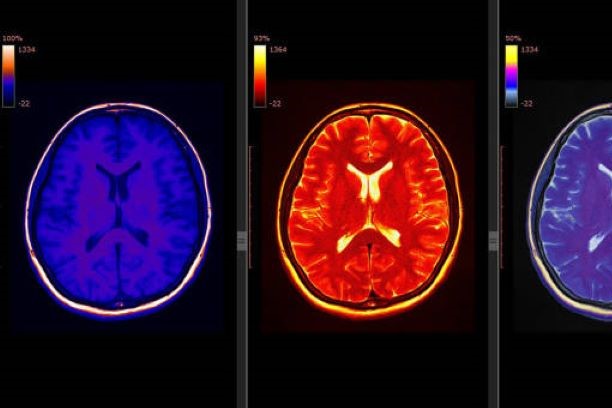

뇌경색은 뇌로 가는 혈류가 차단되면서 뇌세포가 손상되는 치명적인 질환으로, 전 세계적으로 주요 사망 원인 중 하나로 꼽힙니다. 특히 한국에서는 고령화와 서구화된 식습관, 그리고 스트레스가 뇌경색의 주요 위험 요소로 작용하고 있습니다. 뇌경색은 조기 발견과 빠른 치료가 이루어지지 않을 경우 심각한 후유증을 남길 수 있으며, 생명을 위협할 수 있습니다.

뇌경색은 주로 동맥경화와 관련이 있으며, 혈전이나 지방 침전물이 뇌로 가는 혈관을 막아 발생합니다. 주요 원인은 다음과 같습니다.